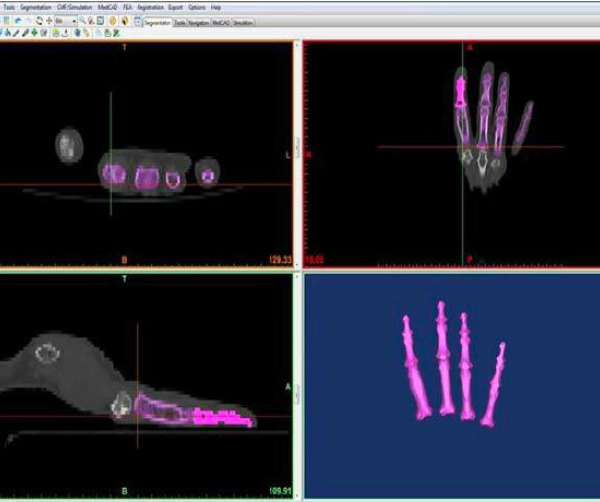

取得醫療影像

根據臨床需求,透過 CT、MRI 或其他醫療影像設備取得病患解剖資料, 作為後續模型製作與分析的基礎。

分割影像與建模

將掃描結果轉換為可列印的 3D 模型,針對重點解剖結構進行分割、整理與輸出, 形成 STL 或 OBJ 等列印檔案。